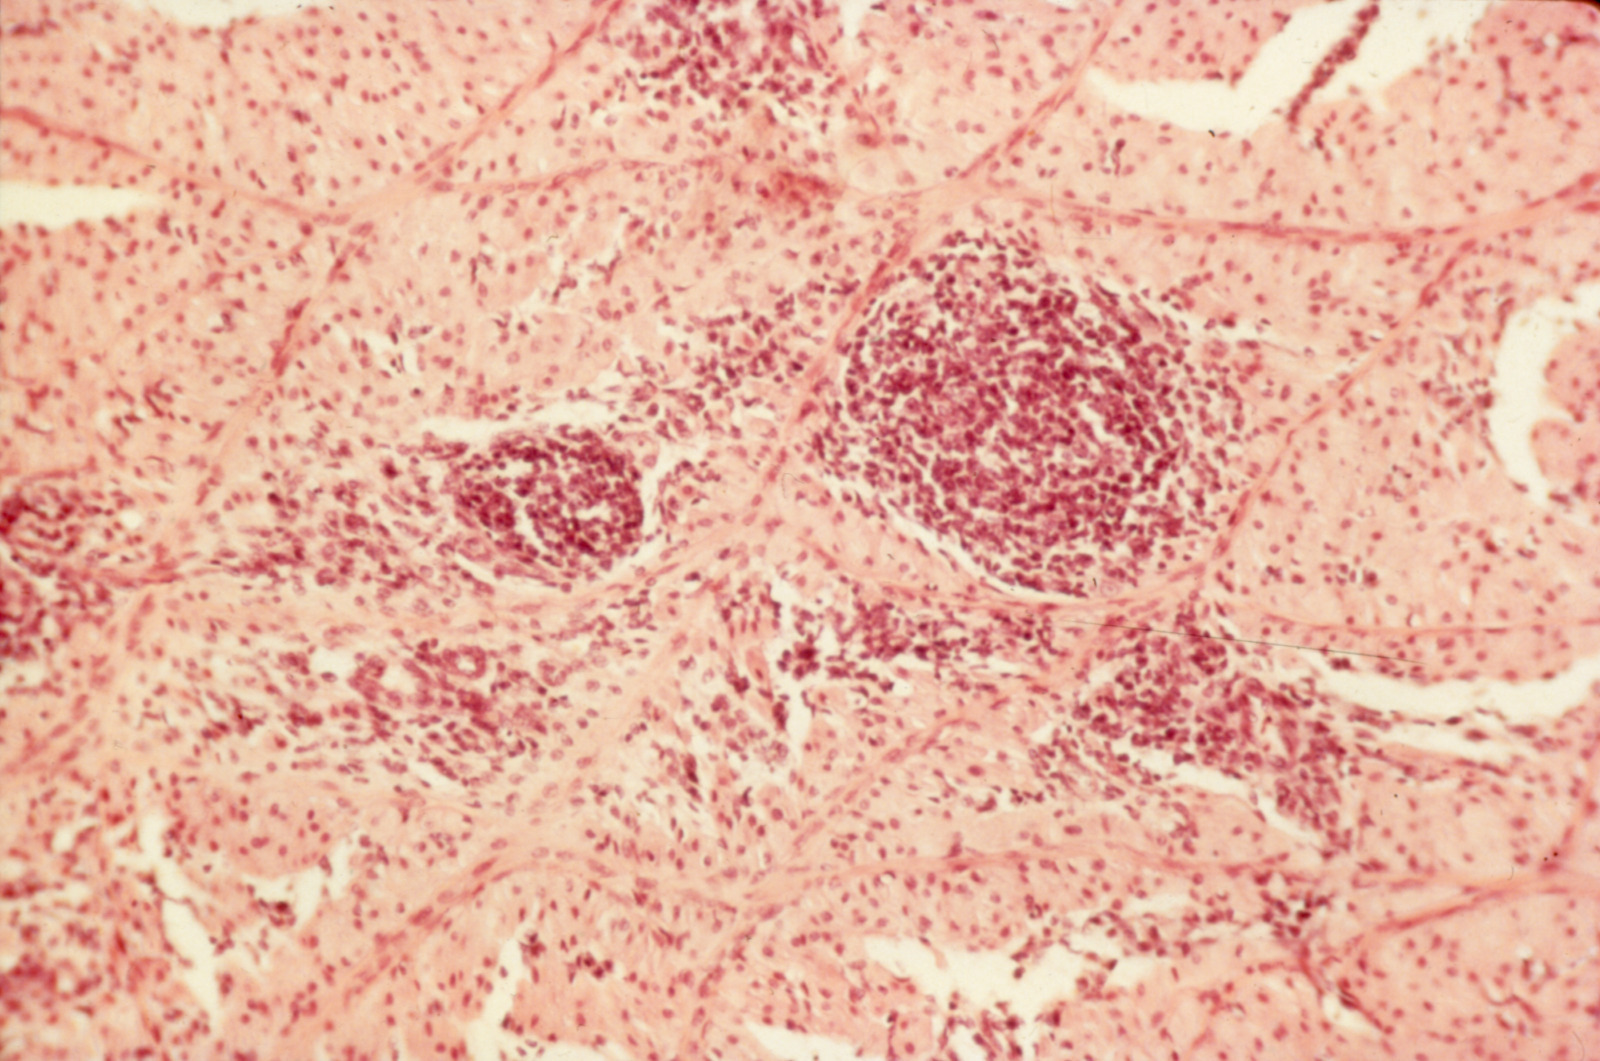

Avian encephalomyelitis (slide study set no. 5)

Avian encephalomyelitis Avian medicine Chickens--Diseases Turkeys--Diseases Pheasants--Diseases

Slide Study Set #5, Avian Encephalomyelitis, 2 sets (includes 32 color slides), 1974